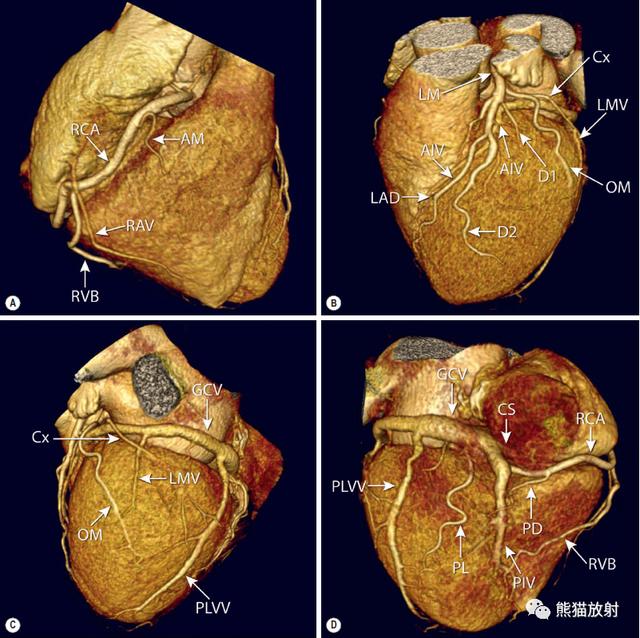

图1 优势冠状动脉

三维容积重建前面观和膈面观显示右冠状动脉优势循环(A)和左冠状动脉优势循环(B)。在右冠优势循环中,后降动脉(PD) 起始于右冠状动脉(RCA) , 在左冠优势循环中, PD起始于回旋动脉(Cx) (B) 。注意在左冠优势循环的情况下, 右冠短小、右房室沟(RAVG) 空虚是正常现象,不要与右冠闭塞混淆。所示主要分支:AM-锐缘支;D-对角支;OM-钝缘支;PL-后侧支;LV-左心室

冠状动脉和心脏静脉解剖的容积重建。冠状动脉和分支:AM-RCA的锐缘支(A) ;Cx-回旋支(B,C) ;D1和D2-第一、第二对角支(B) ;LAD-左前降支(B) ;LM-左冠状动脉主干(B) ;OM-钝缘支(B,C) ;PD-后降支(D) ;PL-起自RCA的后侧支(D) ;RCA-冠状动脉(A,D) ;RVB-右室支(分布于后室间沟远段部分, A,D) 。

心脏静脉:AIV-前室间静脉(B) ;CS-冠状窦(D) ;GCV-心大静脉(C,D) ;LMV-左缘静脉(C) ;PIV-后室间静脉(D) ;PLVV-左室后静脉(C,D) ;RAV-右房静脉直接引流人右心房(A)。